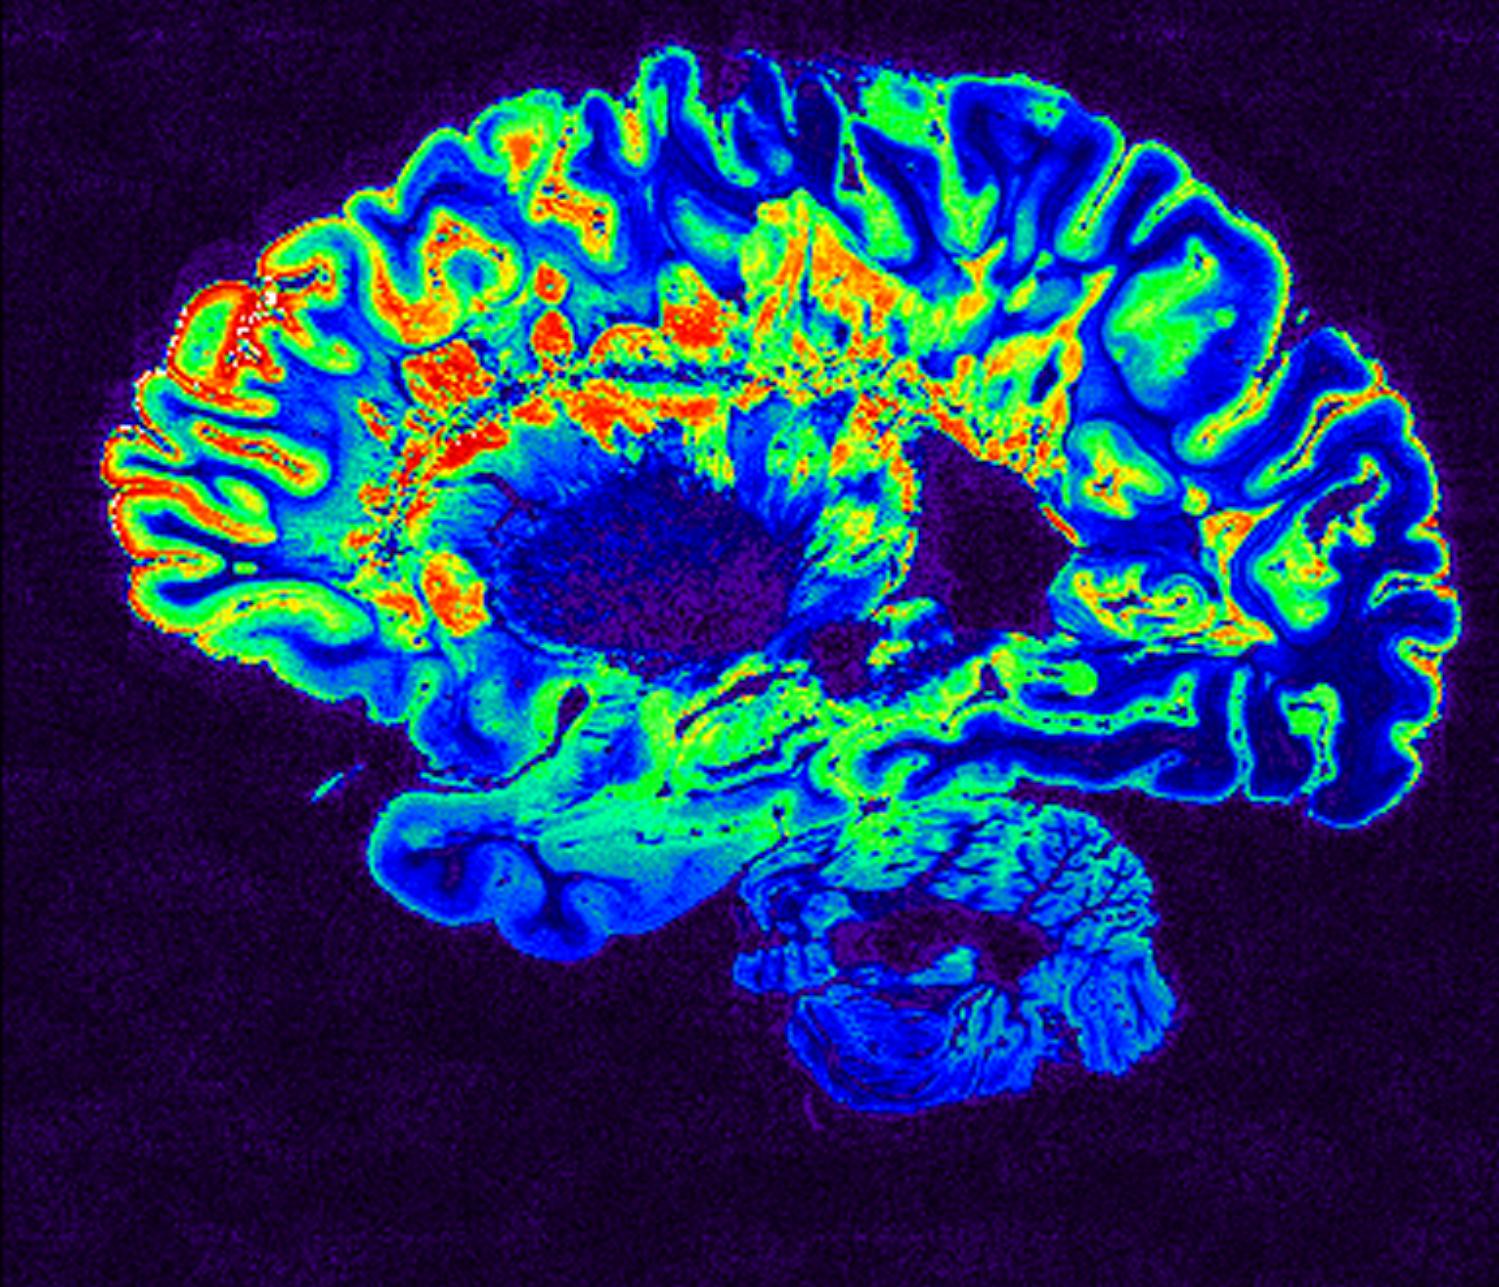

Η σκλήρυνση κατά πλάκας (ΣΚΠ) συχνά αναγνωρίζεται μόνο μετά την εμφάνιση αδιαμφισβήτητων νευρολογικών προβλημάτων, όπως αλλαγές στην όραση ή την ισορροπία. Ωστόσο, μια νέα μελέτη από το Πανεπιστήμιο της Βρετανικής Κολομβίας (UBC) υποδηλώνει ότι το σώμα μπορεί να σηματοδοτεί προβλήματα πολύ νωρίτερα.